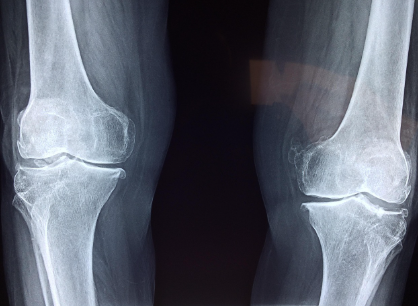

영상 검사

엑스레이로 관절 간격, 연골 소실, 변형 등을 확인하며, 필요시 MRI로 연골 및 인대 상태를 정밀하게 평가합니다.

관절염의 대표적 단계 구분은 켈그렌-로렌스(Kellgren-Lawrence) 분류를 통해 정해집니다.